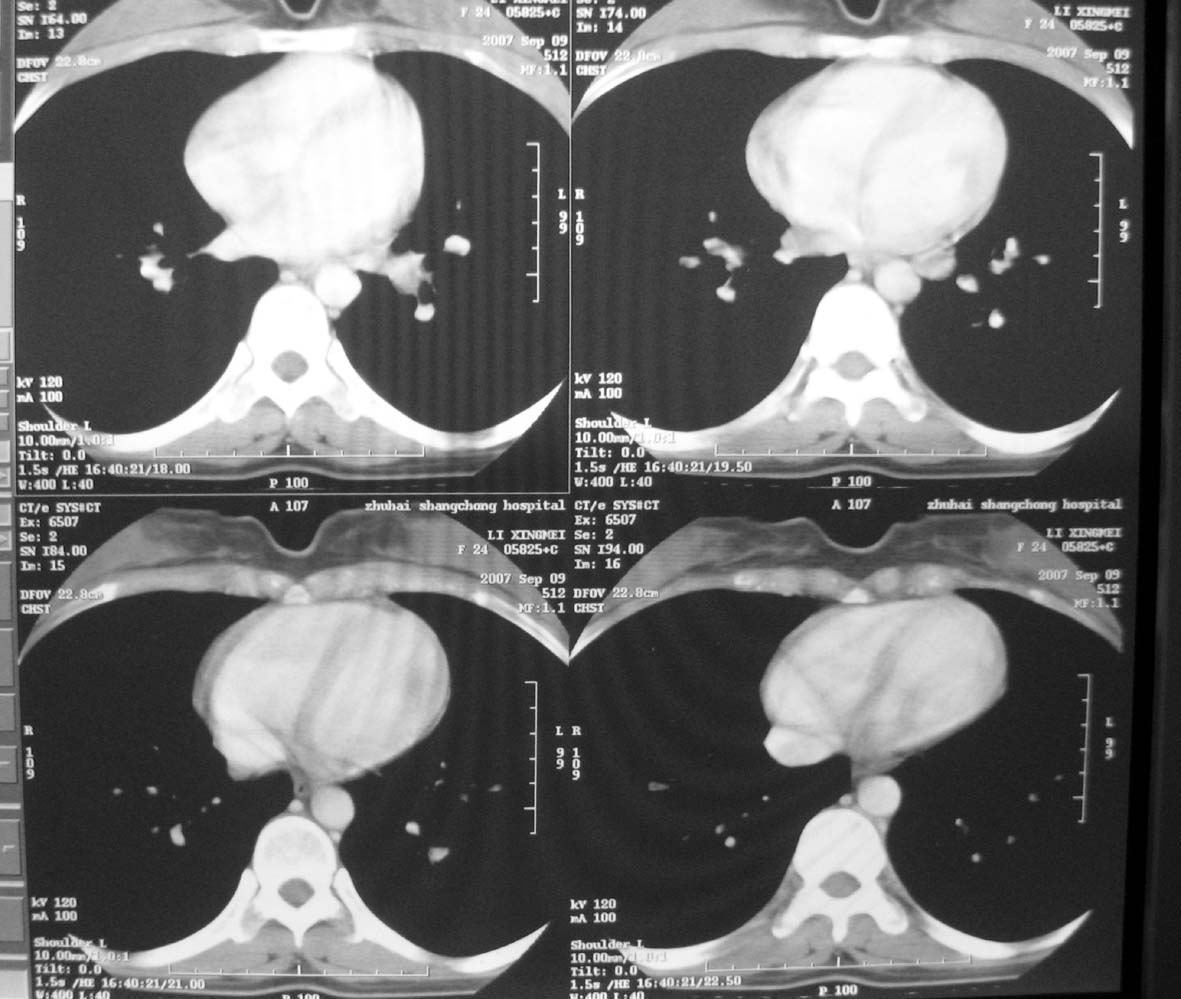

以下是引用qiuleiyu在2007-9-14 19:12:00的发言:[br]纵隔(气管旁组\\隆突下\\主动脉旁组\\血管前组)及肺门淋巴肿大,边界欠清.密度均匀,内无明确钙化.[br]结合临床症状考虑;结节病可能大.[br]鉴别;1,淋巴瘤,可有全身浅表淋巴肿大,肝脾大,发热等.肿大淋巴主要为气管旁组及血管前组及主动脉旁组,肺门肿大不明显.典型者为冰冻纵隔.[br] 2,转移瘤;多见于肺癌,按淋巴链分布肿大,单侧肿大多见,常可见坏死.[br] 3,castlemans;增强后明显血管样强化.内部可有分支状钙化,蜘蛛状瘢痕.周边可有粗大血管.[br] 4,结核;67%有肺部结核灶,肿大淋巴结节,内部可有钙化,增强环状或分格样强化.